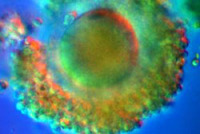

Пока что ваш малыш - это в большей степени идея, чем реальный организм. Его праобраз (точнее, половина праобраза) - это одна из многих тысяч ваших яйцеклеток, находящихся в своей "колыбели" - яичниках. Вторая же половина праобраза (отцовская) еще даже не успела оформиться в зрелый сперматозоид (это произойдет примерно через две недели). Ждем.

Так выглядит яйцеклетка - праматерь всех 100 триллионов (!) клеток вашего будущего ребенка. Красивая, не правда ли?

Так выглядит яйцеклетка - праматерь всех 100 триллионов (!) клеток вашего будущего ребенка. Красивая, не правда ли?Источник иллюстрации: The Visible Embryo